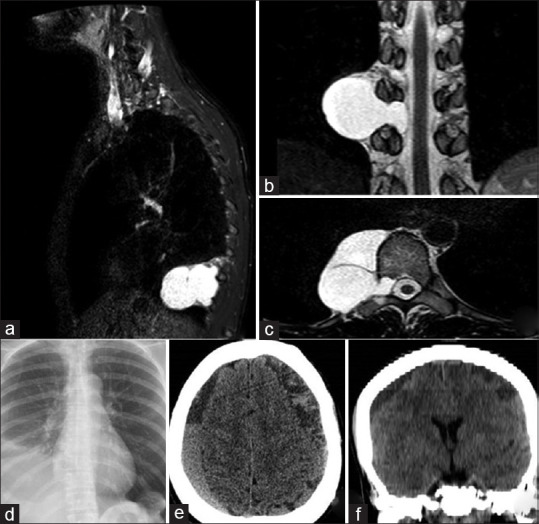

Subarachnoid-pleural fistula (SPF), a rare complication following transthoracic spinal surgery, results in the accumulation of cerebrospinal fluid (CSF) in the pleural space. Hindered spontaneous closure, attributed to negative pleural pressure, gives rise to CSF hypotension and subdural blood collections. Despite numerous reported cases, achieving consensus on management remains elusive. Treatment options encompass conservative measures, surgical repair, epidural blood patch, and diverse approaches such as multilayer dural closure or meningocele resection. Presented herein is a distinctive case following lateral thoracic meningocele surgery, where SPF-induced CSF hypotension found successful resolution through the innovative use of titanium hemostatic clips to occlude the meningocele. This novel approach, emphasizing the utility of titanium clips, deviates from conventional strategies. Surgical SPF exclusion, particularly leveraging titanium clips, emerges as a potential solution, effectively alleviating symptoms of CSF hypotension. The article also aims to present a personal experience, contributing an effective and alternative approach for the etiological treatment of thoracic meningocele.